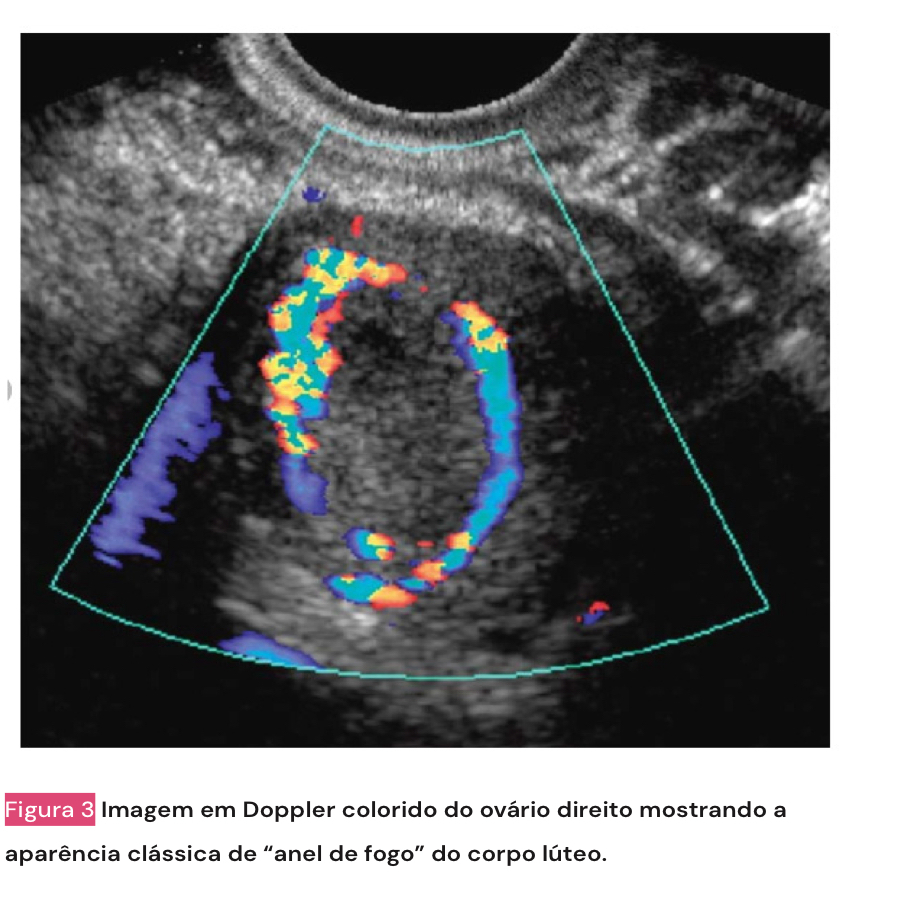

• USG pélvica: ver anatomia uterina e ver presença de corpo lúteo (se tem, ovulou - anel de fogo na USG)